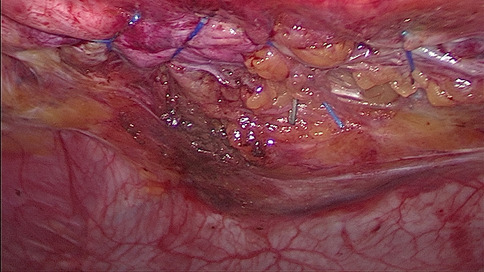

Until now there have been early attempts at producing advanced laparoscopic systems but these have been cumbersome and limited in their engineering. We present a revolutionary new advanced laparoscopic instrumentation system called ArtiSential. The ArtiSential instruments include bipolar forceps, Maryland dissector, monopolar spatula, monopolar hook, needle holder, with more on the way. They allow a wide range of articulating movement through 7 degrees of freedom that can mimic the dexterity of robotic platforms (Fig. 1). Traditional laparoscopic instruments have limited range of movements but these instruments allow for complex articulating movements in different planes which can be further exploited around the fulcrum of the port. This additional articulation means that there is better access to difficult part of anatomy. Furthermore, there is tactile feedback on the instrument handset which is lightweight and disposable.

Our initial series of cases include pelvic colorectal surgery and demonstrate the advantages of articulating instruments (Fig. 2). Further, we demonstrate that there is a learning curve to these instruments to maximise their benefit during complex procedures. We suggest adopting the formal training programme which includes a period of dry lab training before embarking on clinical cases so that surgeons may truly benefit from these advanced instruments. This also allows for safer introduction of new technology.

Advanced laparoscopic instruments such as ArtiSential should be used to make challenging aspects of laparoscopic surgery more accessible. These are not substitute for all straight instruments but best used to maintain precision during difficult manoeuvres in combination with traditional instruments.